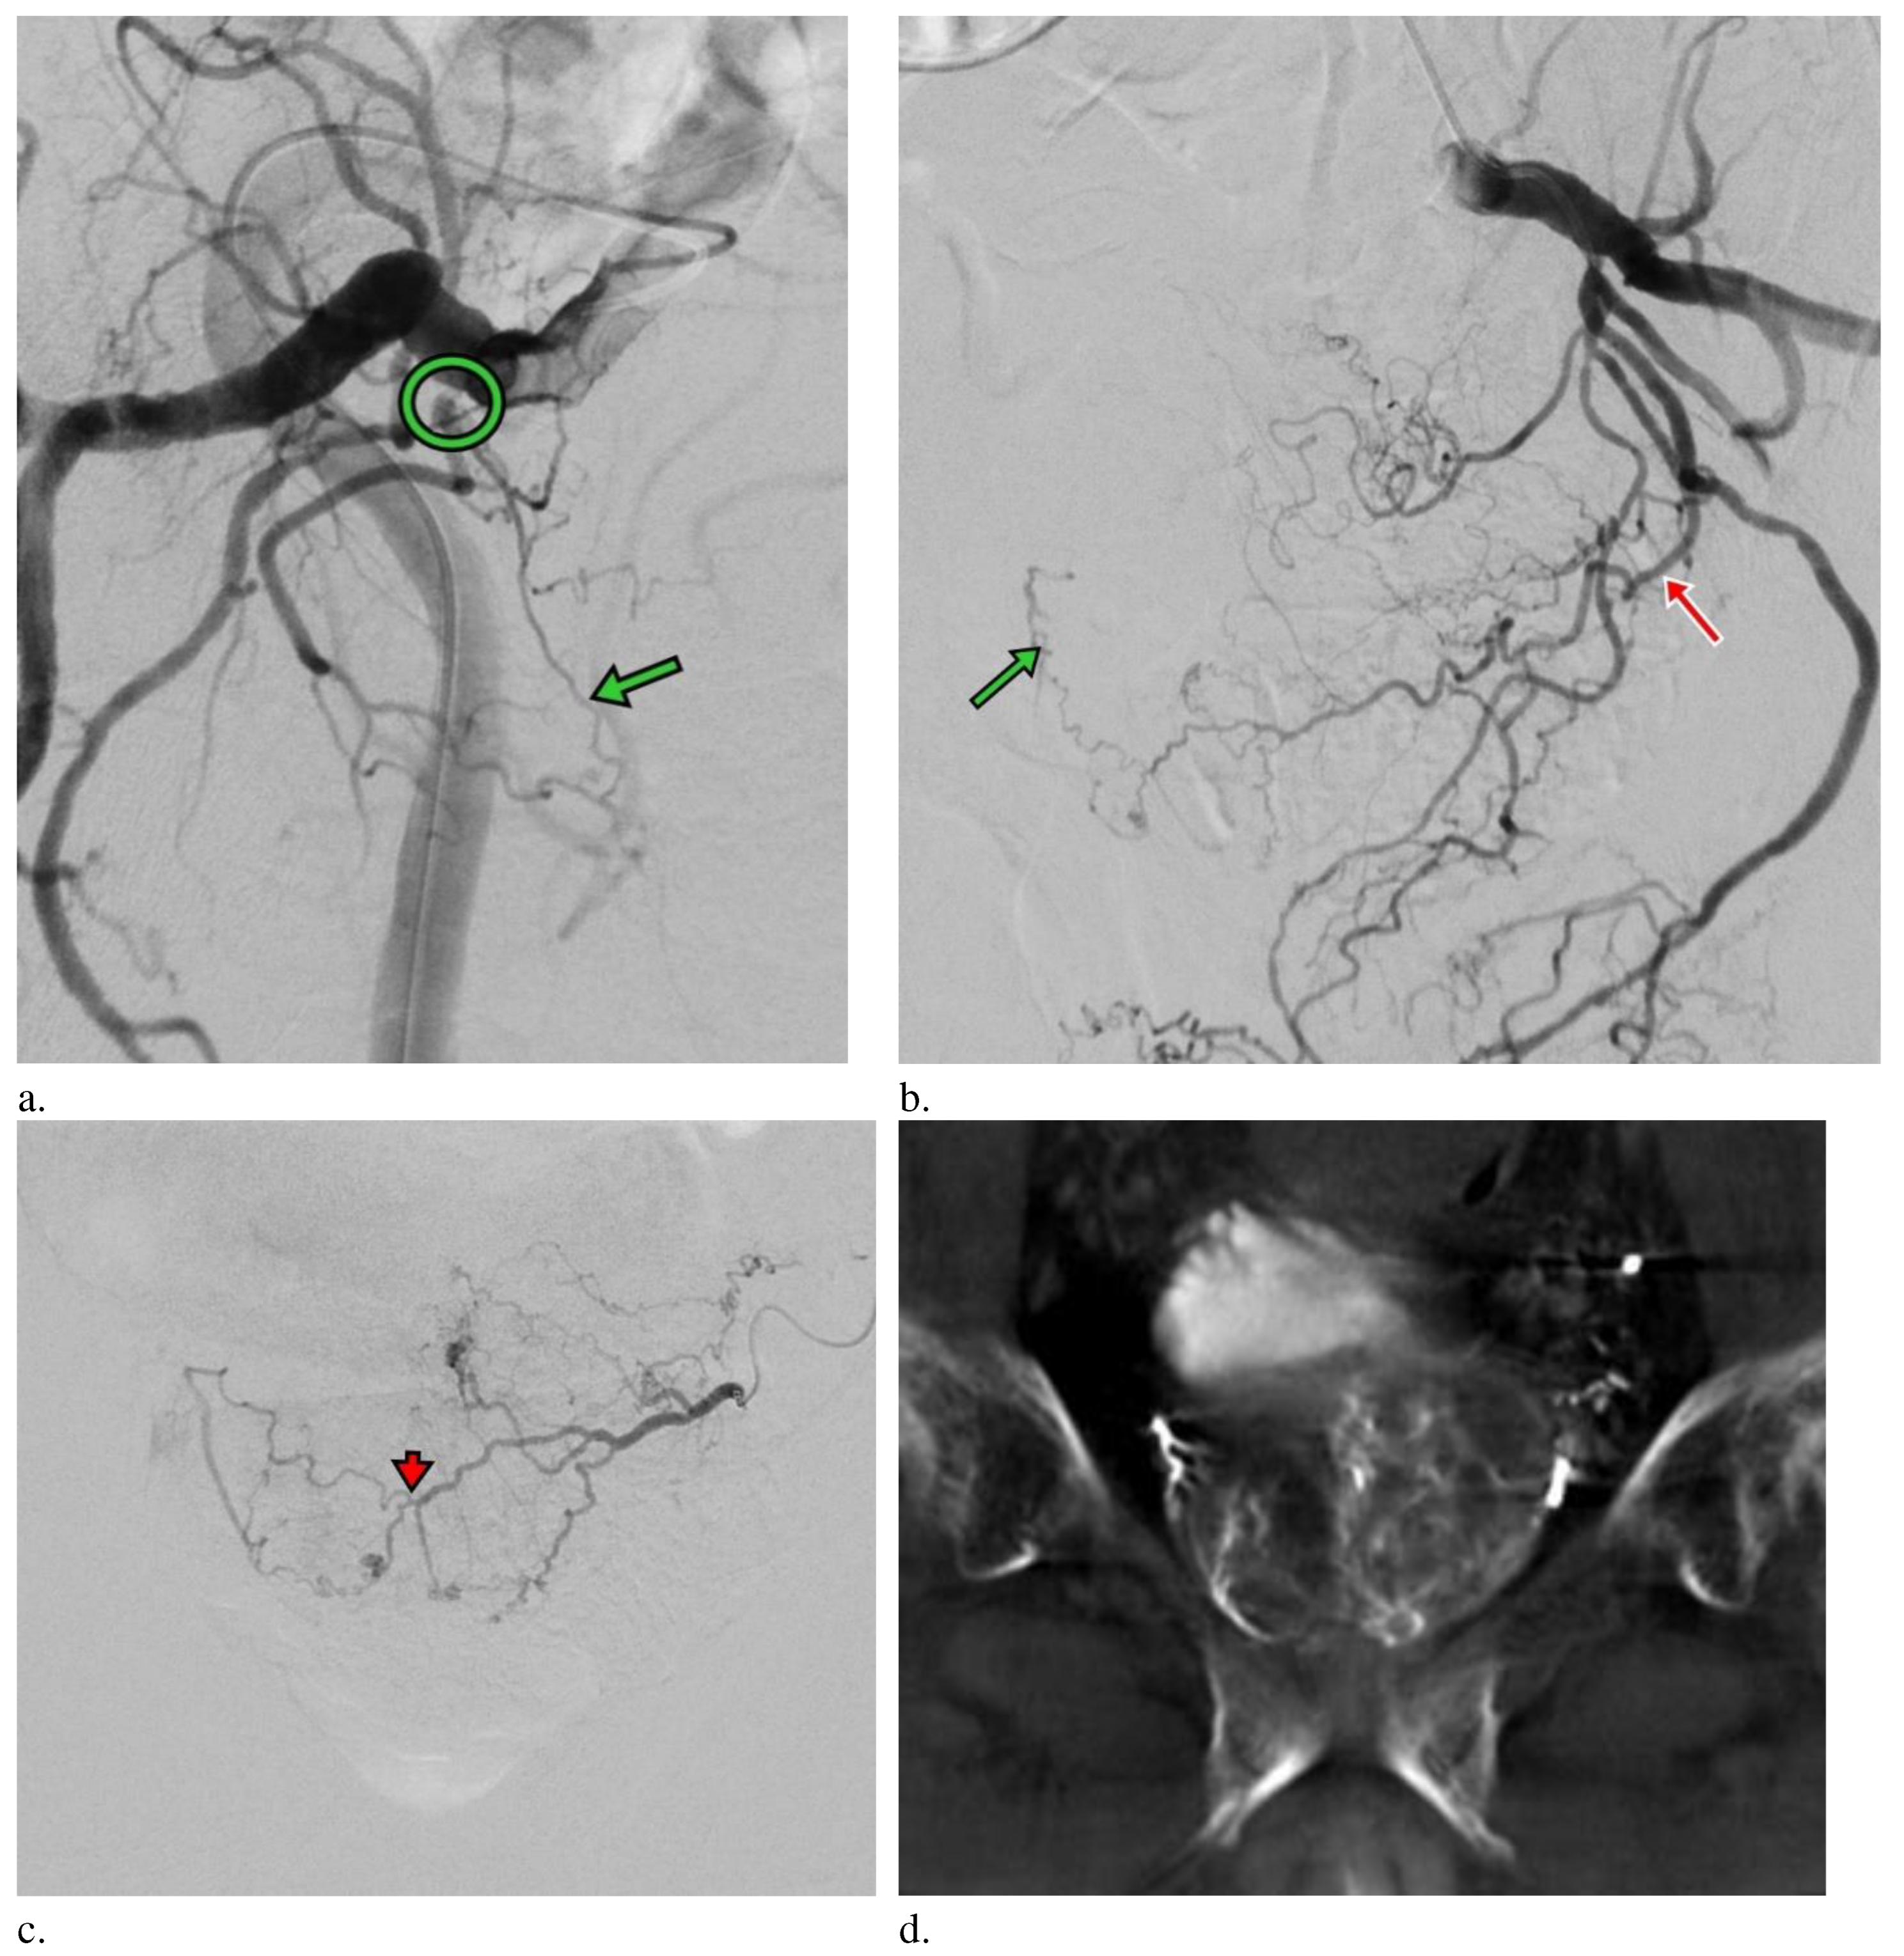

The PAE procedure was done via left distal transradial access (dTRA). After local anaesthesia (LA), 3000IU Heparin was injected via sheath. A 125cm catheter (Ultimate, Merit Medical Inc.) was introduced via distal radial artery straight-down to the common iliac artery and navigated to right internal iliac artery. The procedure was complicated by severe stenosis in right internal iliac artery and microcatheter advancement toward right prostate artery was not feasible. Right femoral access was attempted but again failed due to stenosis. (Figure 2a) Left prostate artery showed both sides prostate perfusion and was accessible uneventfully by a 2.4F microcatheter (150cm Maestro, Merit Medical Inc.) through intraprostatic anastomosis (Figure 2 b-c). A pre-filled syringe of 300-500um Tri-acryl gelatin microspheres (Embosphere, Merit Medical Inc.) was mixed with 10ml iodinated contrast agent, and 1ml of the microsphere was injected slowly until the antegrade flow stopped. Unilateral PAE was performed due to severe stenosis at the right side. Procedural time was 220 min. Haemostasis by compression was 2 hours and bedrest was 4 hours. Patient was discharge on the next day without complication.

Aligned with previous investigations, our report also showed significant LUTS improvement from Severe at baseline to Moderate at 1-month and further down to Mild at 6-month. 78.3% improvement relevant to 18 IPSS points at 1 year and good through 2-year. PAE was demonstrated to be effective to reduce prostate volume of 35% without any complications.7 Although only unilateral prostate artery was selection by microcatheter, both sides PAE was done for this case by cone beam CT(CBCT) image confirm. This is the first reporting image show both sides prostate perfusion by unilateral prostate artery due to severe stenosis on the other side. Although unilateral PAE was done for this case, which was shown to be one of the negative factors for clinical success, the clinical outcomes were found to be comparable to the existing reports.8 In Bilhim et al 2013, bilateral PAE lead to better clinical results but 50% of patients received unilateral PAE also showed a good clinical outcome like this case.8 From our experience, unilateral PAE is considered a technical success and improvement of IPSS 25% or more from baseline is determined as a clinical success. In this case, both technical and clinical successes were achieved, and PAE was shown to be safe and effective for elderly who is eager to treat the bothersome LUTS secondary to BPH. No symptoms recurrence after PAE was identified.

Figure 2. (a) Right internal iliac angiography (oblique view RAO 30 degrees) show high grade stenosis (circle) at branch to the right prostate artery (green arrow) (b) Left internal iliac angiography (oblique view LAO 30 degrees) show the left prostate artery (red arrow) with contrast opacified at right side prostate artery (green arrow) (c) Left prostate angiography (AP view) show both side prostate perfusion via intraprostatic anastomosis (arrowhead). (d) CBCT images showed prostate perfusion at both sides on left prostate angiography.